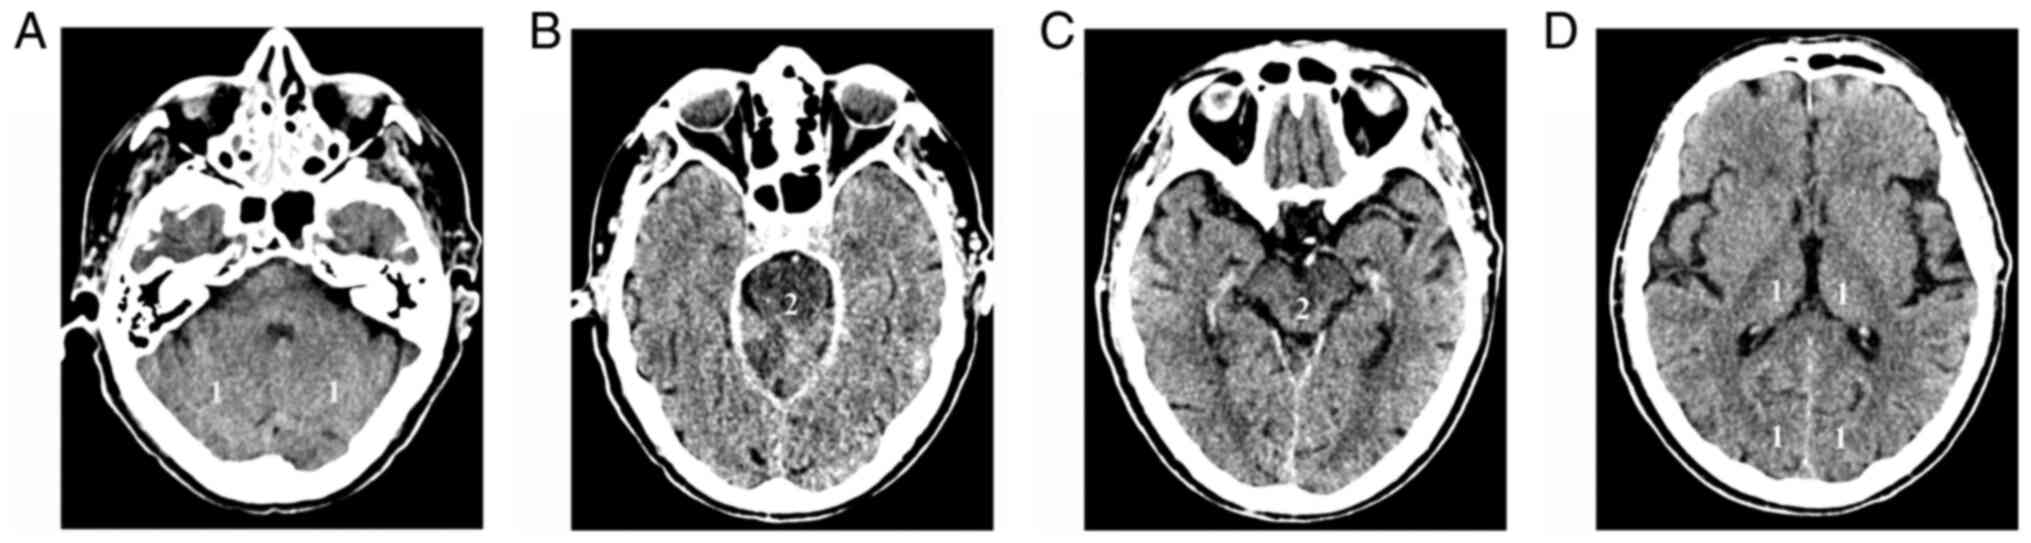

4. Posterior Circulation Acute Stroke Prognosis Early CT Score (pc-ASPECTS)

Figure 2

Axial non-contrast CT images (A) at the level of the cerebellar hemispheres, (B) pons, (C) midbrain and cerebral peduncles, and (D) thalamus, show the allocation of points to each structure for the calculation of pc-ASPECTS. CT, computed tomography; pc-ASPECTS, pc-ASPECTS, Posterior Circulation Alberta Stroke Program Early CT Score.

In patients from the Basilar Artery International Cooperation Study (BASICS) group, a significant association was found between pc-ASPECTS ≥8, favorable outcome, functional independence (mRS ≤2) and reduced mortality (23). However, after adjustment for age, NIHSS and tissue-type plasminogen activator (tPA), only functional independence (RR, 2.0; 95% CI, 1.1-3.8) and mortality (RR, 0.7; 95% CI, 0.5-0.98) were significantly associated, but not a favorable outcome. In a post hoc analysis, the same group was further dichotomized by pc-ASPECTS of <6 and ≥6. It was found that a score of ≥6 was an independent predictor of a favorable outcome, even after adjustment for age, NIHSS, and treatment modality (RR, 3.1; 95% CI, 1.2-7.5) (23). In patients with BAO presenting with coma, the discriminative prognostic power of pc-ASPECTS of <8 OR, ≥8 was not found to be significantly associated with a favorable outcome or mortality, if adjusted for age, NIHSS and treatment modality (24). Even in a larger cohort comprising 231 patients with acute BAO, the prognostic value of pc-ASPECTS in predicting functional independence at 3 months was not significant (25).

Pc-ASPECTS dichotomized by <8 or ≥8 was also evaluated on CT perfusion (CTP) maps in 27 patients from the BASICS registry (26). The most frequent changes were seen in 93% of cases on mean transit time (MTT) parameter maps (95% CI, 76-99). Cerebral blood volume (CBV) pc-ASPECTS <8 was evident in 3 cases, all of whom died. However, none of the perfusion changes were associated with functional outcome, likely due to the small number of available cases (26).